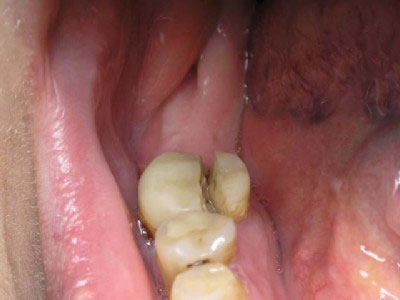

Первую часть задачи по спасению удалось выполнить. Теперь этот зуб будет находиться под наблюдением в течение 3-4 месяцев. После этого срока будет сделан контрольный рентген, который должен показать, насколько успешной была наша попытка спасти зуб от удаления, а именно, мы ожидаем уменьшения очага воспаления вокруг корня. Если эта тенденция будет явно заметна, только тогда будет принято окончательное решение о восстановлении зуба коронкой. А на очереди у этой пациентки сосед-«близнец» этой многострадальной 6-ки, 7-ой нижний зуб. Что тут скажешь?.. Узнаваемый почерк предыдущего доктора.

Во втором случае начиналось все довольно похоже.

Такая же негерметичная пломба, такой же анкерный штифт… при этом твердые ткани сохранены гораздо лучше первого случая. По всему периметру зуба граница полости находится выше уровня десны, а, значит, по крайней мере, прогноз на долговечность реставрации будет вполне оптимистичным.